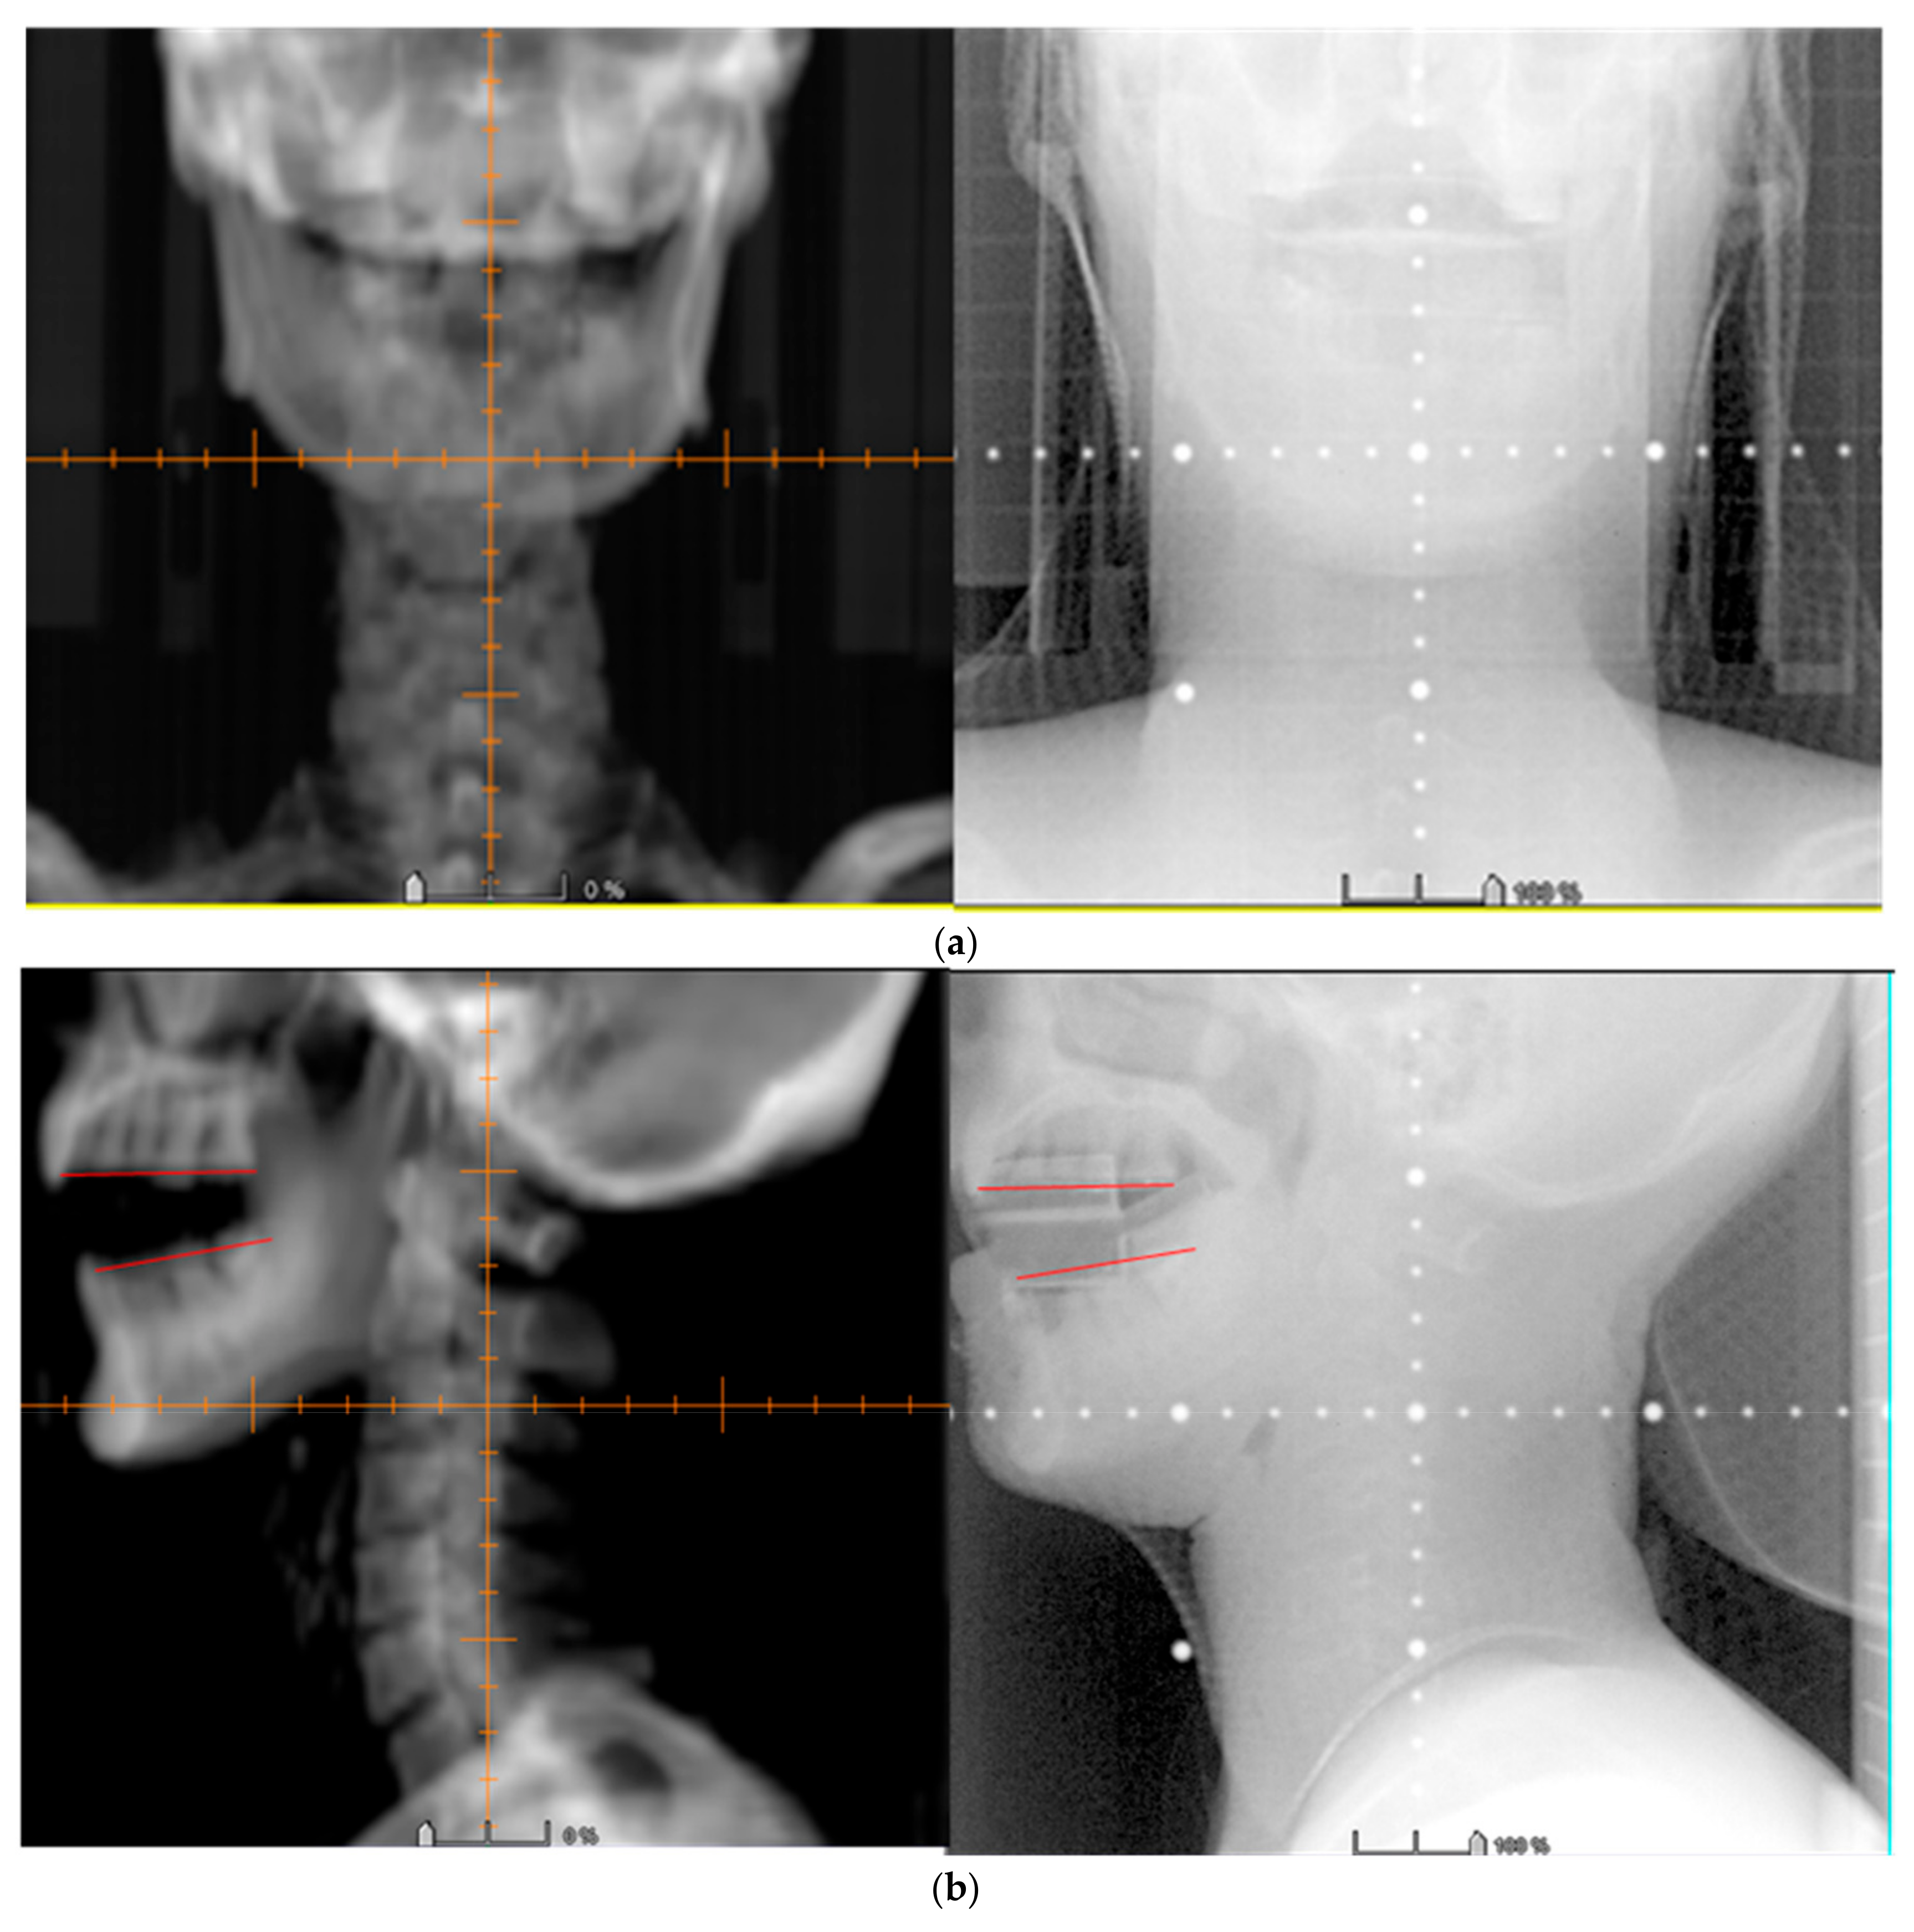

3.3. Image Verification